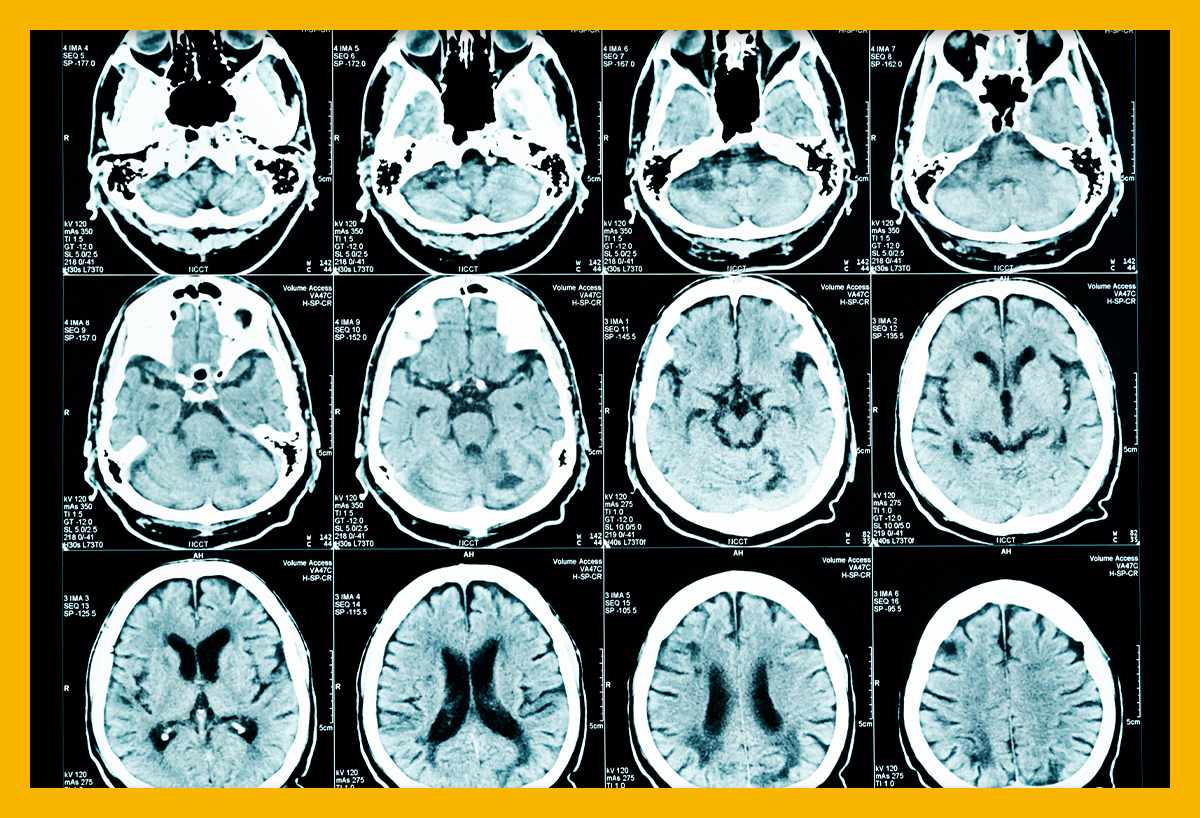

뇌경색이란 무엇인가요?

뇌경색은 뇌의 특정 부위에 혈액이 공급되지 않아 발생하는 문제입니다. 주로 혈관이 막히거나 좁아져 혈액이 제대로 흐르지 않을 때 발생하죠. 전 세계적으로 많은 사람들이 이 질환으로 고통받고 있으며, 특히 노인층에서 빈번하게 발생합니다. 뇌경색을 예방하고 조기에 발견하는 것이 중요한 이유는 이 질환이 뇌에 큰 손상을 줄 수 있기 때문입니다.